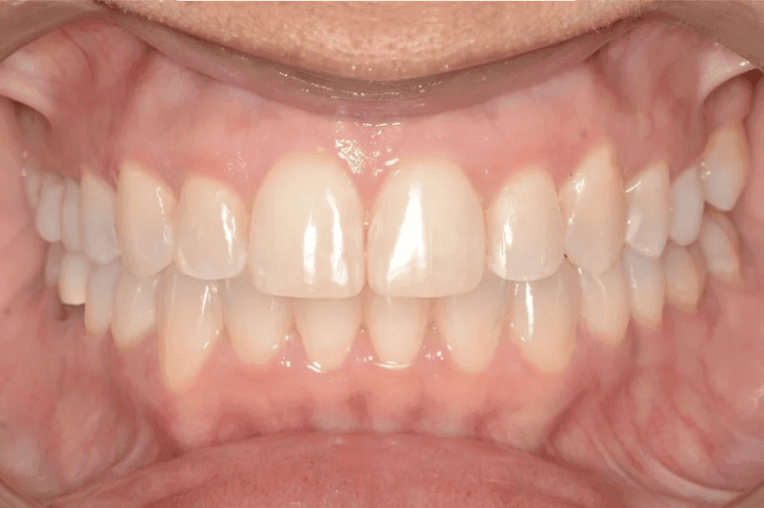

Initial treatment

INTRAORAL

Final results